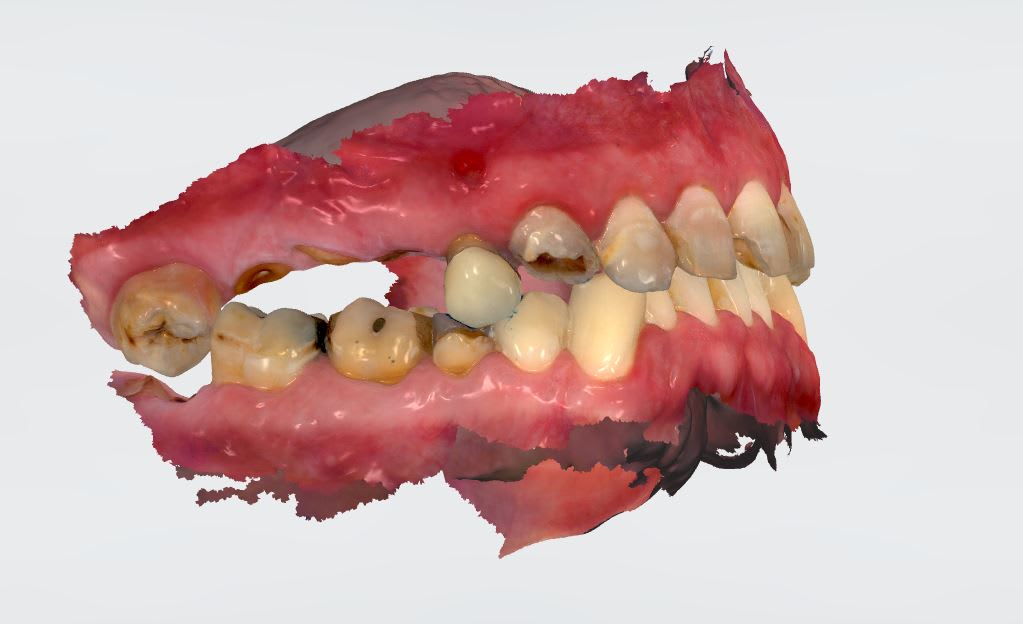

Nouveau patient sympa qui vient au cab car son stellite haut "on voit plus les dent de devant" et "tient plus trop".

La 13 est mobile.

Les dents mandibulaires ne sont pas mobiles, ni sensibles.

Comme vu à la radio, grosse perte de DV.

Non avec des antécédents de soins intensifs et une maladie dentaire diffuse c'est un status complet qu'il faut pour y voir clair. Agrémenté d'une empreinte 3 D pour mater l'occlusion. Demande du patient : "j'aimerais bien qu'on me refasse les dents de devant.".